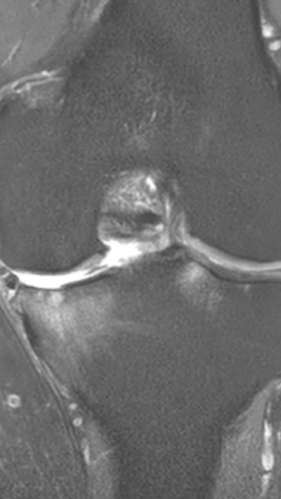

Асептический некроз коленного сустава

4 процедуры ФДТ, 9 процедур MBST, 15 процедур ИПМТ

Параметры изменяются в зависимости от процедуры

Дата публикации: 22.08.2025 14:27:03

3 процедуры ФДТ, 9 процедур MBST, 15 процедур ИПМТ

Дата публикации: 22.08.2025 14:26:54